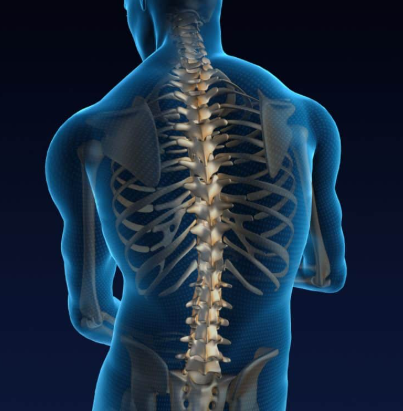

척추 전방전위증은 척추의 특정 마디가 제자리에서 앞으로 밀려나면서 신경을 압박하는 질환입니다. 주로 요추 4번과 5번 사이에서 자주 발생하며, 심한 경우에는 허리 통증뿐 아니라 다리 저림, 감각 이상, 보행 불편 등의 신경 증상이 동반될 수 있습니다.

척추는 여러 개의 뼈(척추체)와 디스크, 인대, 근육이 정교하게 맞물려 안정성을 유지하는데, 이 중 하나라도 약해지면 구조적 불균형이 생기게 됩니다. 척추 전방전위증은 이 균형이 무너진 대표적인 예로, 척추를 잡아주는 심부근육이 약화된 상태에서 자주 나타납니다.

건강한 척추는 옆에서 보면 S자 형태를 유지합니다. 하지만 전방전위증이 생기면 하부 요추가 앞으로 밀리며 이 곡선이 깨지고, 허리 뒤쪽 근육이 과도하게 긴장해 통증이 발생합니다.

척추 전방전위증의 진행이 심하면 척추관이 좁아지면서 좌골신경통 같은 신경성 통증이 동반되기도 합니다. 이는 단순히 허리 근육 문제를 넘어선 신경적 불편함으로 이어질 수 있어 조기 관리가 중요합니다.